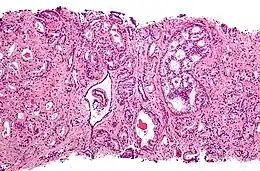

Histologie

Le diagnostic est obtenu par des biopsies prostatiques multiples, réalisées de manière échoguidée et par voie transrectale. Elle permet également de réaliser le score de Gleason, de grande valeur pronostique.

.jpg) Adénocarcinome prostatique

Adénocarcinome prostatique.jpg) Adénocarcinome prostatique

Adénocarcinome prostatique- Adénocarcinome ; tissus indifférenciés

- Invasion périneurale par un adénocarcinome prostatique. HE, x400

Anatomopathologie

Le cancer entreprend la portion périphérique de la glande, au contraire de l'hypertrophie prostatique bénigne qui intéresse la zone centrale, périurétrale.

Score de Gleason

La structure tissulaire des cancers de la prostate varie des formes différenciées (cellules cancéreuses ressemblant aux cellules saines), dite de grade 1, aux formes les moins différenciées (cellules cancéreuses présentant beaucoup de caractères atypiques par rapport aux cellules saines), dite de grade 5.

Plusieurs grades peuvent se rencontrer au sein d'un même tissu. Le score de Gleason est calculé de la façon suivante : on additionne les deux grades les plus représentés de la tumeur. Le premier chiffre représentant le score du contingent le plus représenté. Ainsi 4+3 est plus péjoratif que 3+4

Si la somme est de 6 ou moins, le cancer est dit bien différencié, donc de meilleur pronostic ; 7 : le cancer est moyennement différencié ; 8 ou plus : le cancer est peu différencié, donc de moins bon pronostic.